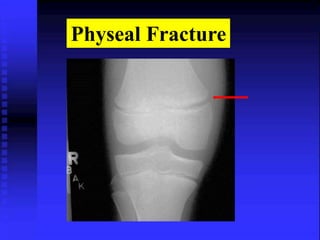

Physeal Fracture

Early stage of ossification Another variation of normal

Normal

Fracture